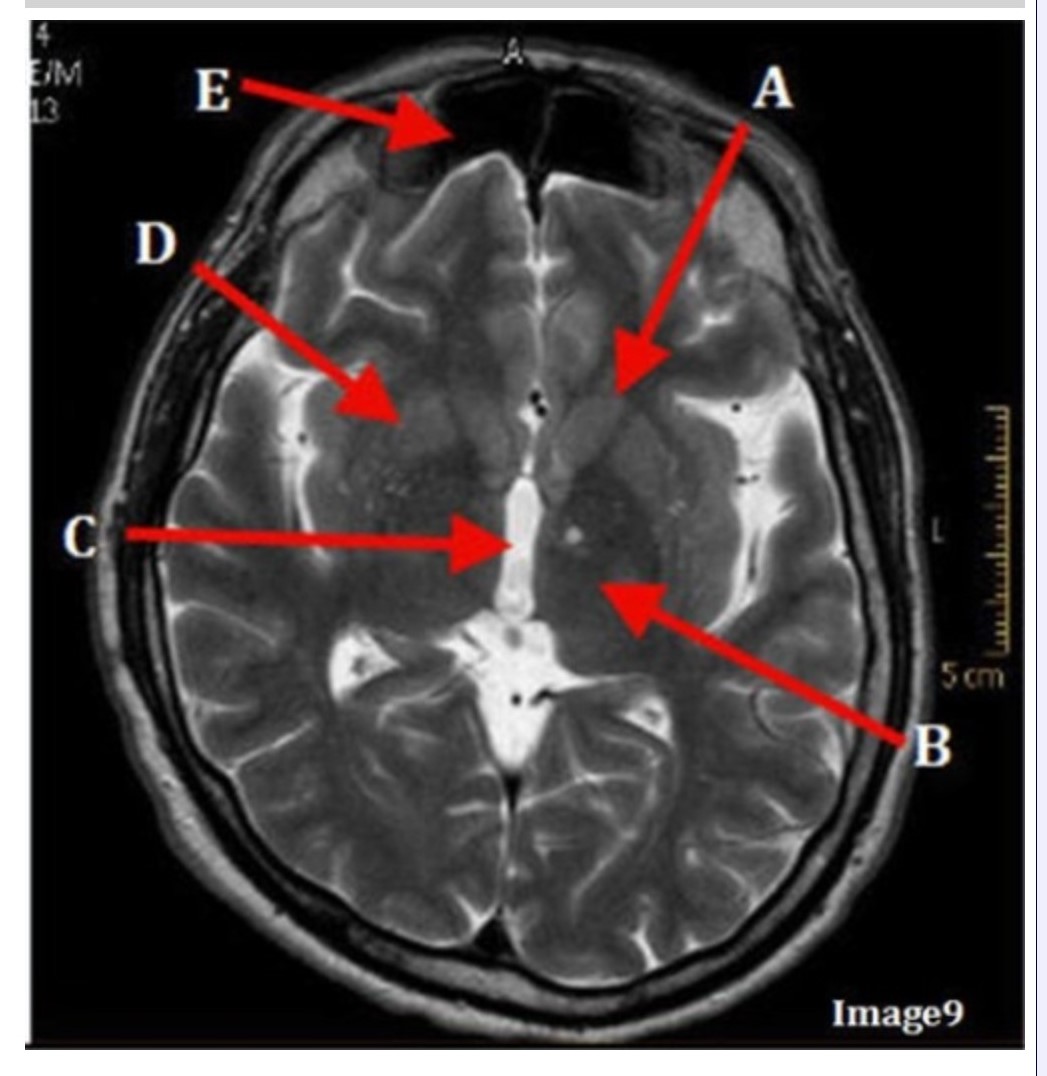

Letter C in Image 9 is pointing to:

A. Third ventricle

B. Thalamus

C. Lentiform nucleus

D. Caudate nucleus

Letter B in Image 9 is pointing to:

A. Third ventricle

B. Thalamus

C. Lentiform nucleus

D. Caudate nucleus

Letter D in Image 9 is pointing to:

A. Third ventricle

B. Thalamus

C. Lentiform nucleus

D. Caudate nucleus

Letter E in Image 9 is pointing to:

A. Maxillary sinus

B. Sphenoid sinus

C. Frontal sinus

D. Ethmoid sinus

Letter A in Image 9 is pointing to:

A. Third ventricle

B. Thalamus

C. Lentiform nucleus

D. Caudate nucleus

Image 9 is an example of a _____ weighted sequence acquired in the _______ scan plane.

A. T1; Axial

B. T2 FLAIR; Sagittal

C. T2; Axial

D. T2; Coronal